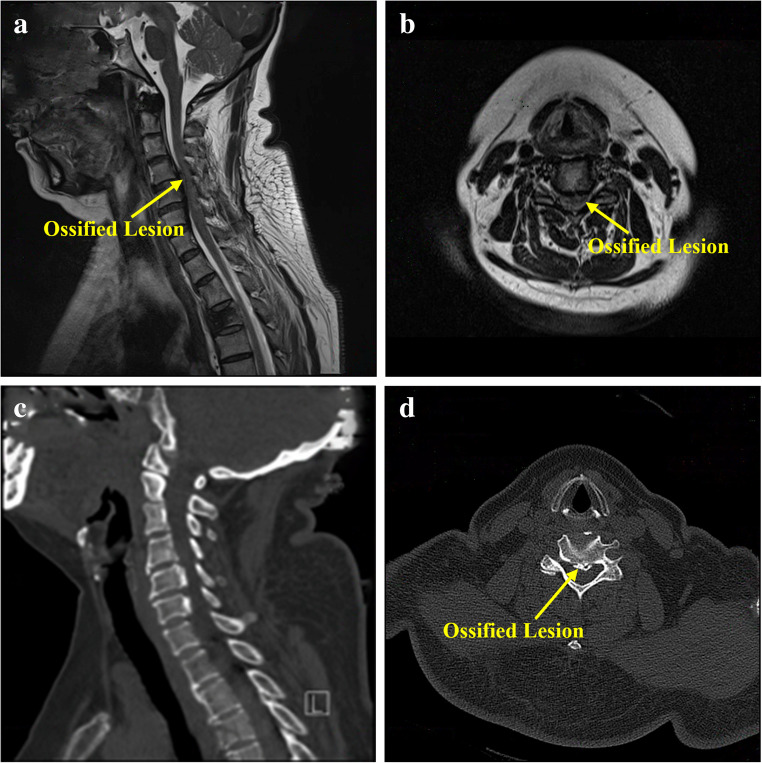

Cervical ossification of the posterior longitudinal ligament (OPLL) causes spinal cord compression due to spinal canal stenosis. Traditional anterior approaches such as anterior cervical discectomy and fusion (ACDF) and anterior cervical corpectomy and fusion (ACCF) have limitations, including restricted decompression range, extensive vertebral resection trauma, or insufficient stability. This study aimed to evaluate the efficacy and safety of a novel surgical technique-Anterior Cervical V-Slot Decompression and Fusion (ACVDF)-for treating long-segment OPLL. A retrospective analysis was conducted on 30 patients with multilevel OPLL who underwent ACVDF between December 2021 and March 2024. A curved grinding drill was used to precisely remove portion of the vertebral body and ossified tissue (≤ 50% of the sagittal diameter) through the V-shaped distracted intervertebral space, achieving direct decompression of long-segment OPLL During surgery. Postoperative follow-up 14.70 ± 1.62 months (12-18 months). Clinical outcomes were assessed using the Japanese Orthopaedic Association (JOA) score, visual analog scale (VAS) score, and imaging methods such as CT and MRI. All 30 patients successfully completed the surgery, with a mean operative time of 143.17 ± 10.96 min and intraoperative blood loss of 177.67 ± 49.45 ml. At the final follow-up, the JOA score improved from 8.50 ± 1.96 to 14.67 ± 0.71 (P < 0.05), with an excellent and good rate of 90.00%. The VAS score decreased from 6.53 ± 1.53 to 1.30 ± 0.79 (P < 0.05). The spinal canal occupancy rate decreased from 42.13 to 10.61% (P < 0.05). The Height of the fused segments was 62.70 ± 13.58 mm at 1 week postoperatively and increased to 62.94 ± 13.99 mm at the final follow-up (P > 0.05). Cervical range of motion (ROM) decreased from 51.57 ± 8.96° preoperatively to 33.07 ± 6.18° at the final follow-up (P < 0.05). The fusion rate reached 100% at the final follow-up. No complications such as dural tears or spinal cord injuries occurred during surgery. ACVDF can achieve direct decompression of long-segment OPLL while preserving anterior column structures, maintaining cervical stability, and getting favorable clinical outcomes. This technique provides a new safe and effective treatment option for long-segment OPLL.